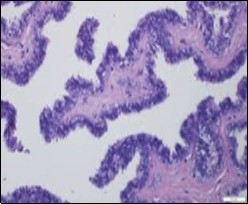

Alternatively, cutaneous ciliated cyst can be lined by non ciliated cuboidal or columnar epithelium with intermingled intercalated, dark or round peg cells. Foci of squamous metaplasia can be occasionally exemplified in the adherent epithelium whereas mucinous cells or apocrine-like features are exceptional 6, 8. Figure 1, Figure 2, Figure 3, Figure 4, Figure 5, Figure 6, Figure 7, Figure 8, Figure 9, Figure 10, Figure 11, Figure 12. 11, 12, 13, 14, 15, 16, 17, 18, 19.

Figure 3.Ciliated cutaneous cyst with a coating of plump, ciliated columnar epithelium and a circumscribing fibro - connective tissue (12).